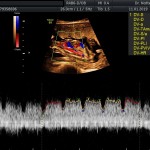

- La vitalidad fetal (Doppler fetal).

- El Doppler de las arterias uterinas maternas y determinación de riesgo y prevención para pre eclampsia severa.